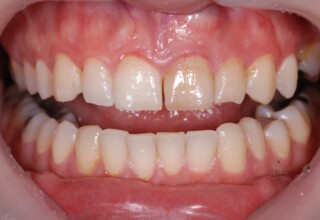

Whitening of non-vital teeth

Teeth with a root canal often lose their brightness and darken to an unesthetic level. Their bleaching requires an excellent root canal and patience. An adhesive filling is placed inside the root to confine the bleaching effect to the tooth part which is visible in the oral cavity. The actual bleaching may require 1-5 short sessions for the placement and renewal of the bleaching material. After the bleaching a high quality adhesive filling is mandatory.

Initial appearance